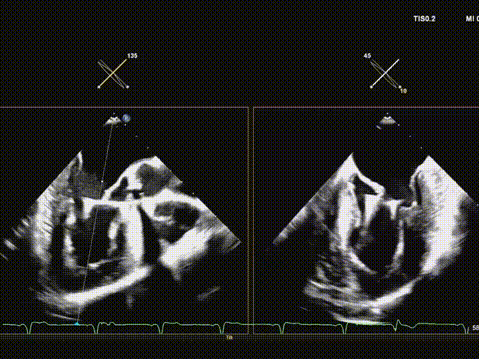

术后超声评估,瓣膜位置深度满意,形态可,微量瓣周漏,最大血流速度1.53m/s,平均跨瓣压差4mmHg。

华正东教授在术后总结中指出,全超声引导TAVR技术在避免放射线及造影剂相关肾损伤方面具有独特优势,特别适用于合并肾功能不全的高危患者。在本例手术中,超声影像清晰引导了导丝跨瓣、球囊预扩、瓣膜输送与释放等关键步骤,展现了其在复杂解剖条件下实现精准介入的可靠性。

术后超声提示人工瓣膜功能良好,平均跨瓣压差仅4mmHg,血流动力学改善显著。值得一提的是,术中选用的Evolut PRO瓣膜系统凭借其可回收、可重新定位的设计特点,为术中调整释放位置提供了重要技术支持,确保了瓣膜的稳定锚定与功能良好。此例手术的成功,充分展现了全超声引导TAVR在治疗二叶式主动脉瓣狭窄方面的可行性与安全性,为华中地区开展绿色介入技术积累了宝贵经验。